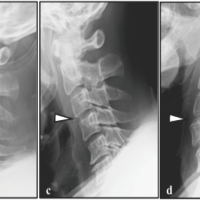

Given the stable nature of the fracture, absence of displacement, and good functional status, a conservative treatment approach was adopted. The patient was advised to maintain strict non-weight-bearing for 6–8 weeks, followed by partial weight-bearing ambulation with crutches. She was also prescribed calcium and vitamin D supplementation and advised on physiotherapy, activity modification, and nutritional optimization. At the 8-week follow-up, the patient reported significant improvement in pain and functional mobility. By 12 weeks, she had achieved pain-free full weight-bearing ambulation. At the 6-month follow-up, an MRI was repeated, which showed complete resolution of marrow edema and full consolidation at the fracture site, with no evidence of cortical disruption or delayed union [Fig. 3 and 4].

Figure 3: Magnetic resonance imaging done after 6 months of the treatment showing no changes in the upper part of the femur.

Figure 4: Magnetic resonance imaging report of the left thigh done after 6 months of the treatment.